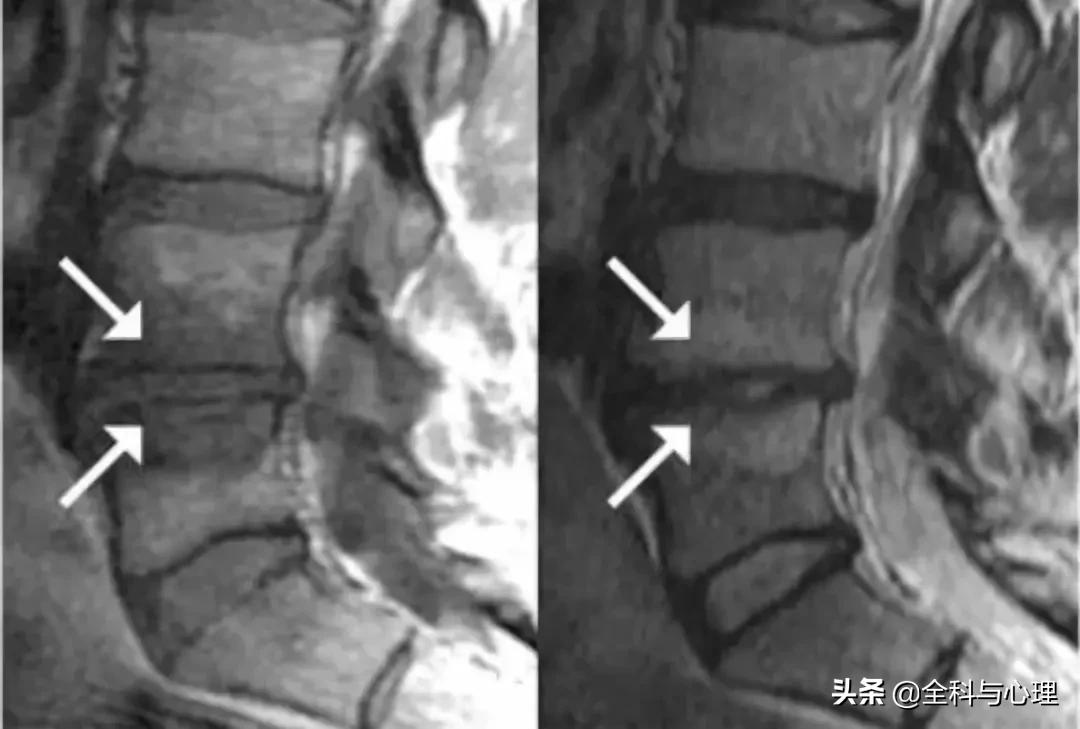

Modic 1 型 (T1 低信号,T2 高信号):终板区水肿表现

Modic 2 型 (T1 高信号,T2 等信号或轻度高信号):终板区脂肪沉积

Modic 3 型 (T1,T2 均低信号):终板区骨质硬化,单纯 3 型很少见。箭头所指为 3 型表现,L4,L5 椎体上缘的后半部分及 S1 上缘为 Modic 2 型改变。